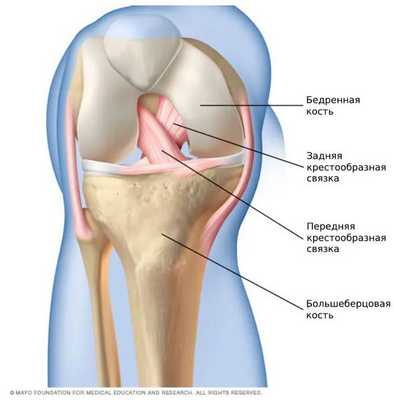

Передняя крестообразная связка (лат. lig. cruciatum anterius) начинается от задневерхней части внутренней поверхности наружного мыщелка (костного выступа) бедренной кости, пересекает полость коленного сустава и прикрепляется к передней части передней межмыщелковой ямки большеберцовой кости также в полости сустава. Крестообразная связка стабилизирует коленный сустав и не дает голени чрезмерно смещаться вперед, а также удерживает наружный мыщелок большеберцовой кости. Задняя крестообразная связка коленного сустава (лат. lig. cruciatum posterius) начинается от передневерхней части боковой поверхности внутреннего мыщелка бедра, пересекает коленный сустав и прикрепляется к задней межмыщелковой ямке большеберцовой кости. Она стабилизирует коленный сустав, и удерживает голень от смещения назад.